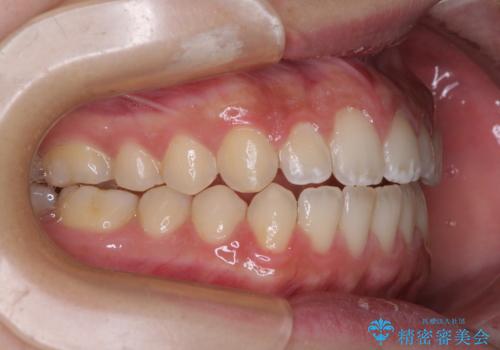

仕上がりとしては、もう少し上下前歯を接触させたかったのですが、ここまで改善されたことで患者様は大変満足され、治療を終えることとなりました。